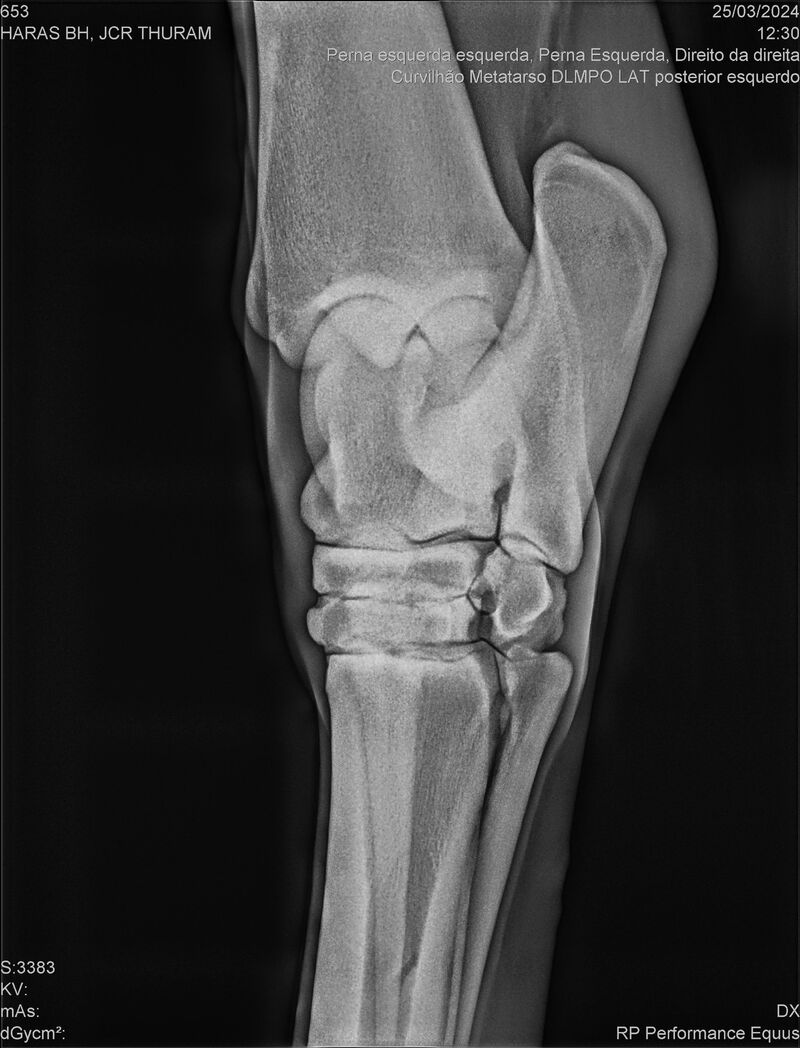

JCR THURAM

Raça: BRASILEIRO DE HIPISMO

Sexo: CASTRADO - CASTRADO

Nascimento: 10/01/2021

Altura Aproximada: 1,58

Pel.: CASTANHO

Registro: 27531-BH

Vend.: HARAS BH

Local : VINHEDO/SP